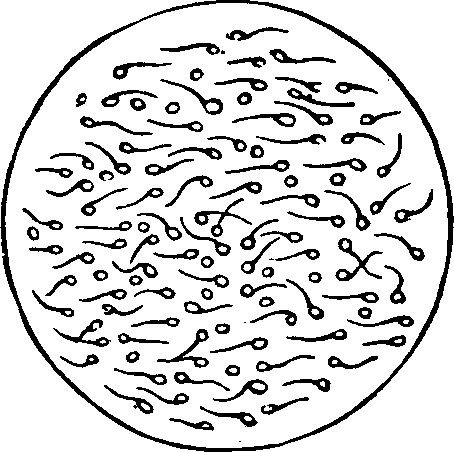

Generation. So long as the vital principle remains in the sperm-cell, it lies dormant. That part of the cell which contains this principle is called the spermatozoön, which consists of a flattened body, having a long appendage tapering to the finest point. If it be remembered that a line is the one-twelfth part of an inch in length, some idea may be formed of the extreme minuteness of the body of a human spermatozoön, when we state that it is from 1/800 to 1/600 part of a line, and the filiform tail 1/50 of a line, in length. This life-atom, which can be discerned only with a powerful magnifying glass, is perfectly transparent, and moves about by executing a vibratile motion with its long appendage. Within this speck of matter are hidden the multifarious forces which, under certain favorable conditions, result in organization. Magnify this infinitesimal atom a thousand times, and no congeries of formative powers is perceived wherewith to work out the wonders of its existence. Yet it contains the principle, which is the contribution on the part of the male toward the generation of a new being.

Fig. 1. A. Human

Spermatozoön magnified about 3,800 diameters. B. Vertical and

lateral views of spermatozoa of man. C, D, E, F. Development of

spermatozoa within the vesicles of evolution. G. Cell of the sponge

resembling a spermatozoön. H. Vesicles of evolution from the

seminal fluid of the dog in the parent cell I. Single vesicles of

different sizes. J. Human spermatozoön forming in its cell.

K. Rupture of the cell and escape of the spermatozoön.